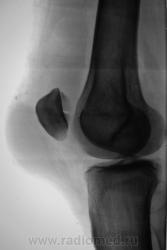

перелом надколенника( редко такой встречается) препателярная гемабурса, гемартроз, сильно пострадала суставная поверхность надколенника

Наверно все таки пателля бипартита. Представить, чтобы так красиво и ровно откололось - трудно... А мягкотканный компонент знатный...

Сам думал о "бипарцита", кстати, недавно был случай с "трипарцита". Но в данном случае был в растерянности, клиника "зашкаливает", конечно, возможно из-за мягкотканного компонента.

В минус травме говорит такая "красивенькая форма" отломка? НО при бипарите про мягкотканный компонент я данных ненашел..